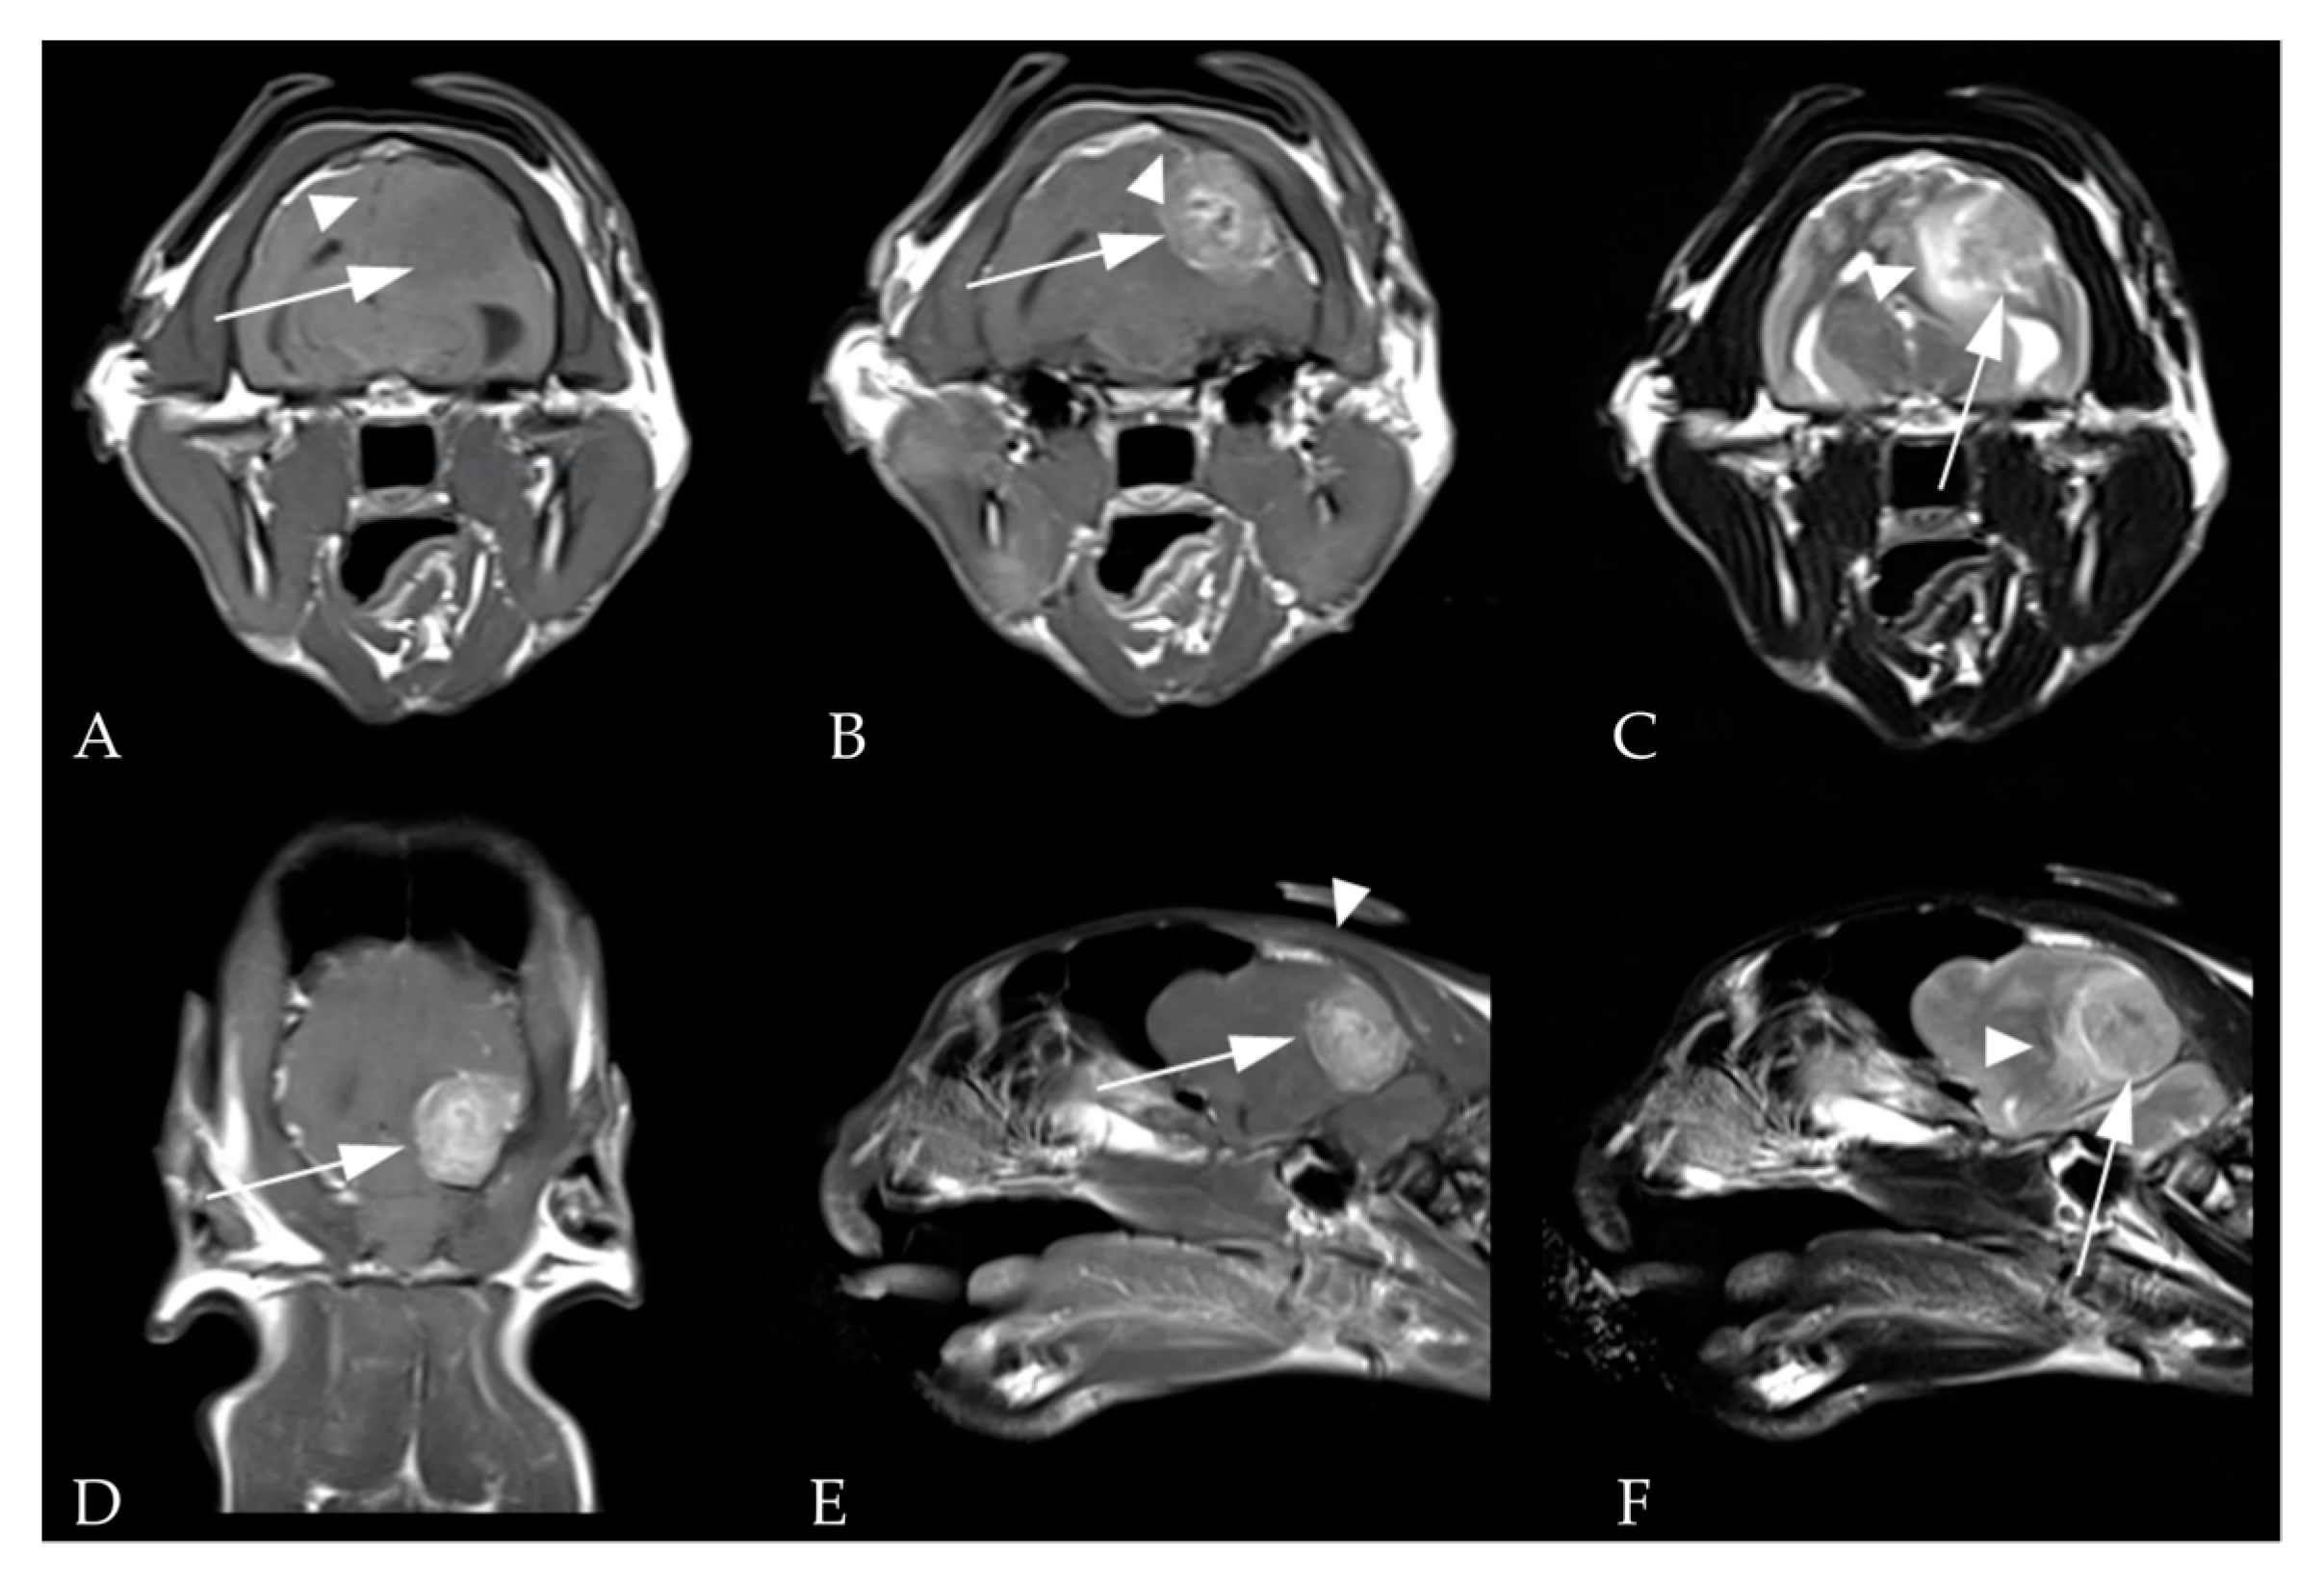

2.2. Images